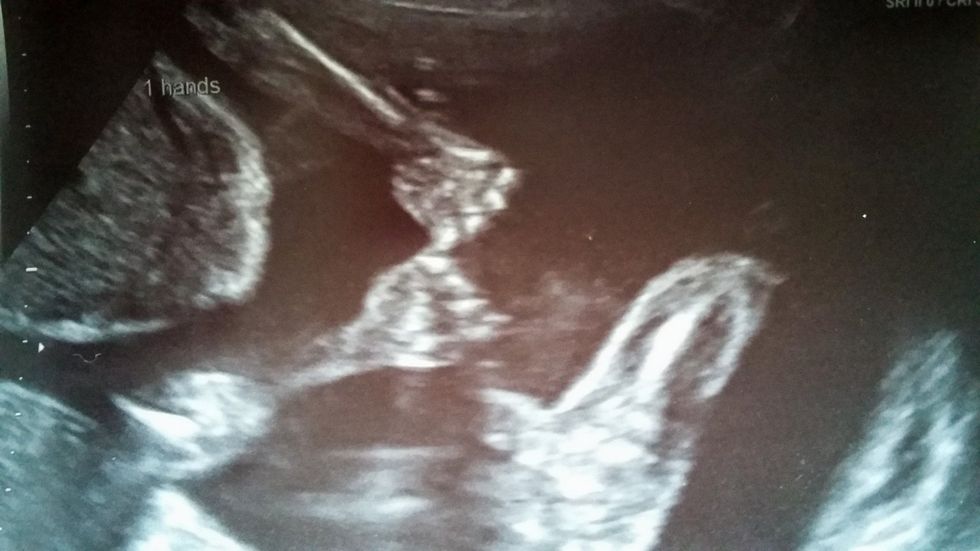

Në një fotografi të bërë me rreze X, është parë teksa binjakët qëndrojnë të mbështetur, si dhe mbahen për dore.

Përndryshe, rreth qafës së tyre mund të mbështillet korda e kërthizës dhe t’ju ndalojë furnizimin me ajër dhe ushqim. Por, ata kanë shpëtuar pasi janë kapur për dore dhe nuk kanë bërë rrotullime.